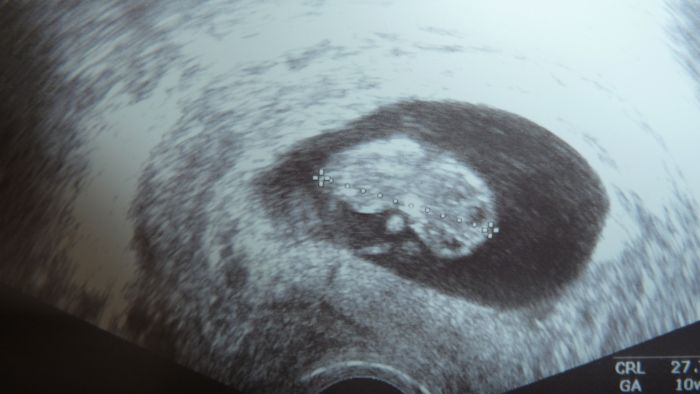

Konečně dnešní návštěva za mnou. Strašně jsem se bála, ale vše je ok, dle ms 9+3, dle utz 10+0. Když jsem řekla, že mi je špatně a zvracím, tak je to prý dobře, tak jsem myslela, že ho vezmu židlí :-D. Konečně mám poprvé v životě průkazku. Jen má špatný přístroj, tak je fotečka špatně vidět. Prcek má 27,76mm. A co jsem říkala, že mám pořád špinění, tak to prý není špinění, ale vaginální mikóza, jak do mě teď pořád šátrali, že stačí něco na rukavici či tak a je to raz dva, tak jsem dostala gel Lactofeel. Kontrola za 3 týdny. Výsledky krve na 1. Teď ve čt 1.malý screaning a v pátek genetika.